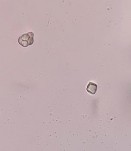

Tinh thể calci oxalat hình cầu gai |

Sợi kèm tinh thể | |

Hạt tinh bột hình chuông |

Tinh thể calci oxalat hình khối |

Mạch mạng |

Khối nhựa mang màu |

Mảnh mô mềm |

Hình 4.17. Soi bột lá Đinh lăng vật kính 40X